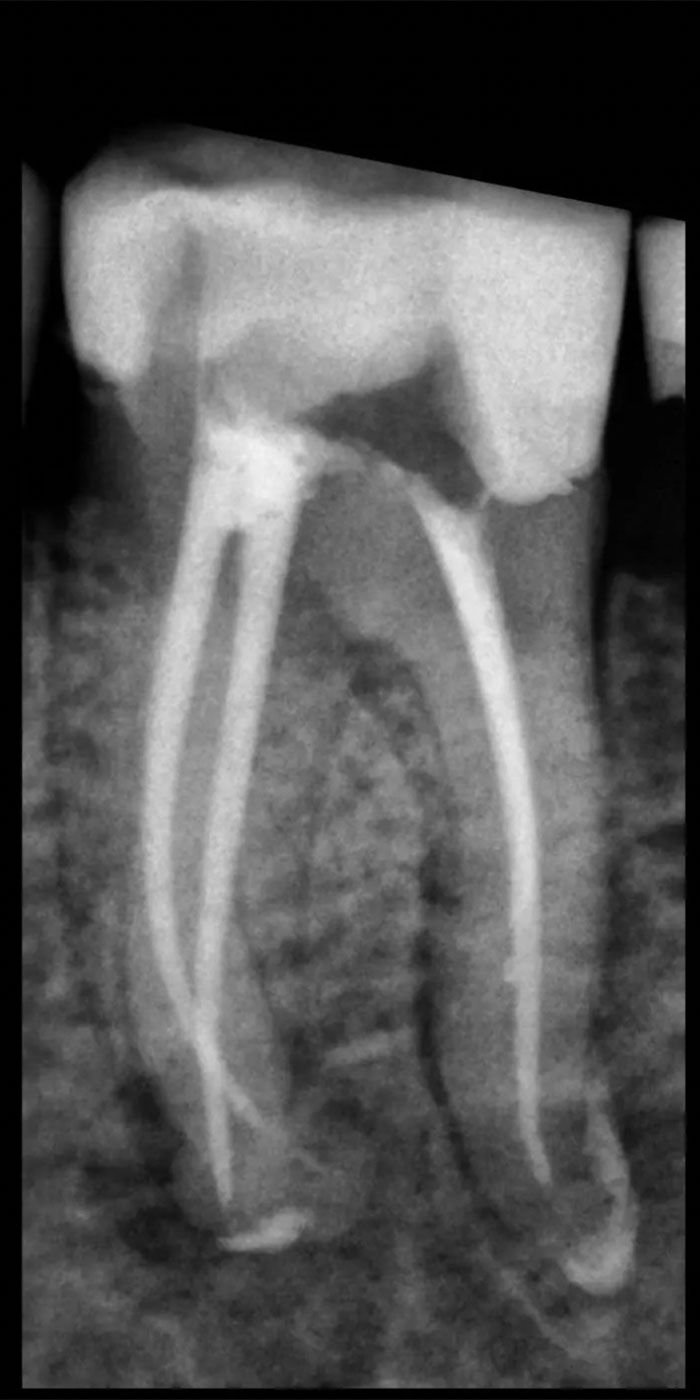

- Our skilled Schenectady root canal dentists will perform a thorough examination and X-rays to assess the extent of damage or infection within the tooth.

- The cleaned canals are then filled with a biocompatible material known as gutta-percha, sealing them to prevent further infection.